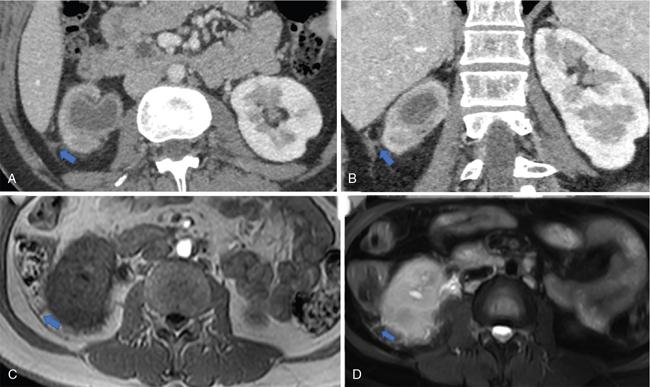

Fig. 10.17.1.4 Contrast-enhanced axial and sagittal CT sections in a case of acute right pyelonephritis (A and B); the right kidney appears bulky with perinephric fat stranding. Thickening of the perinephric bridging septae (blue arrows in A and B) and posterior renal fascia. Axial T1W and axial STIR images also depict the thickened perinephric bridging septae (blue arrows in C and D).